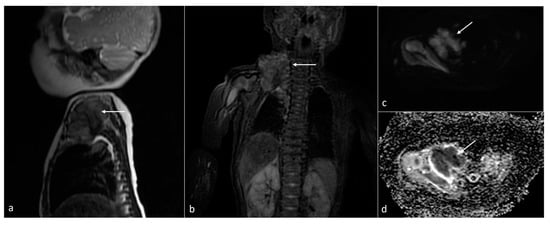

| Neuroblastoma | adrenal gland/infrarenal space | 5 | 11.9 [2.6–24.2] | yes (3/5) (754–1200) | solid/mixed | yes (2/5) | yes (3/3) |